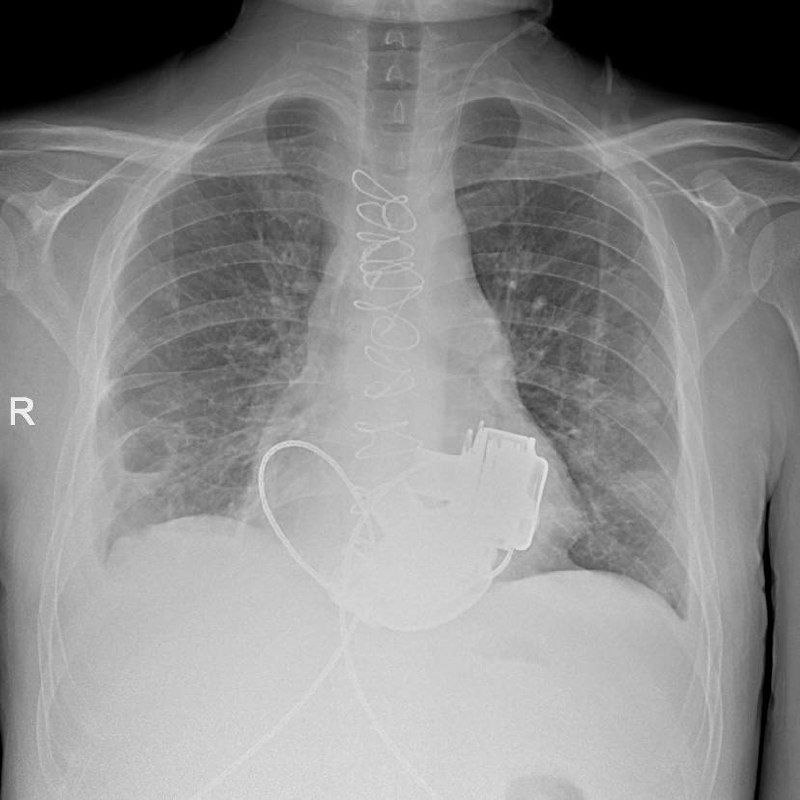

В Мариинской больнице готовят к выписке 36-летнего мужчину, которому имплантировали два искусственных желудочка сердца — редчайшая и высокотехнологичная операция.

Хирурги приняли решение установить систему искусственных желудочков — по сути, это устройство полностью берёт на себя насосную функцию сердца. После такой операции у человека нет привычного пульса, потому что кровоток становится непрерывным, а не толчкообразным.